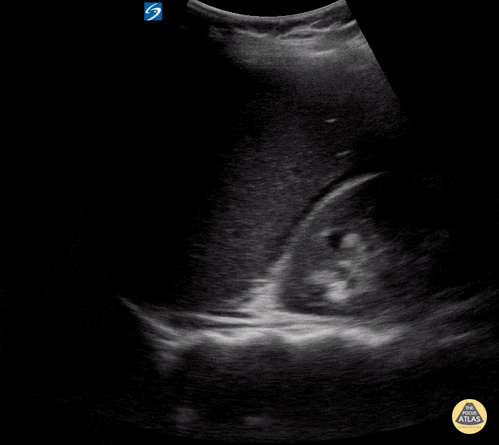

Peds-Trauma

abnormalluq, abnormalruq, msk, traumanormal